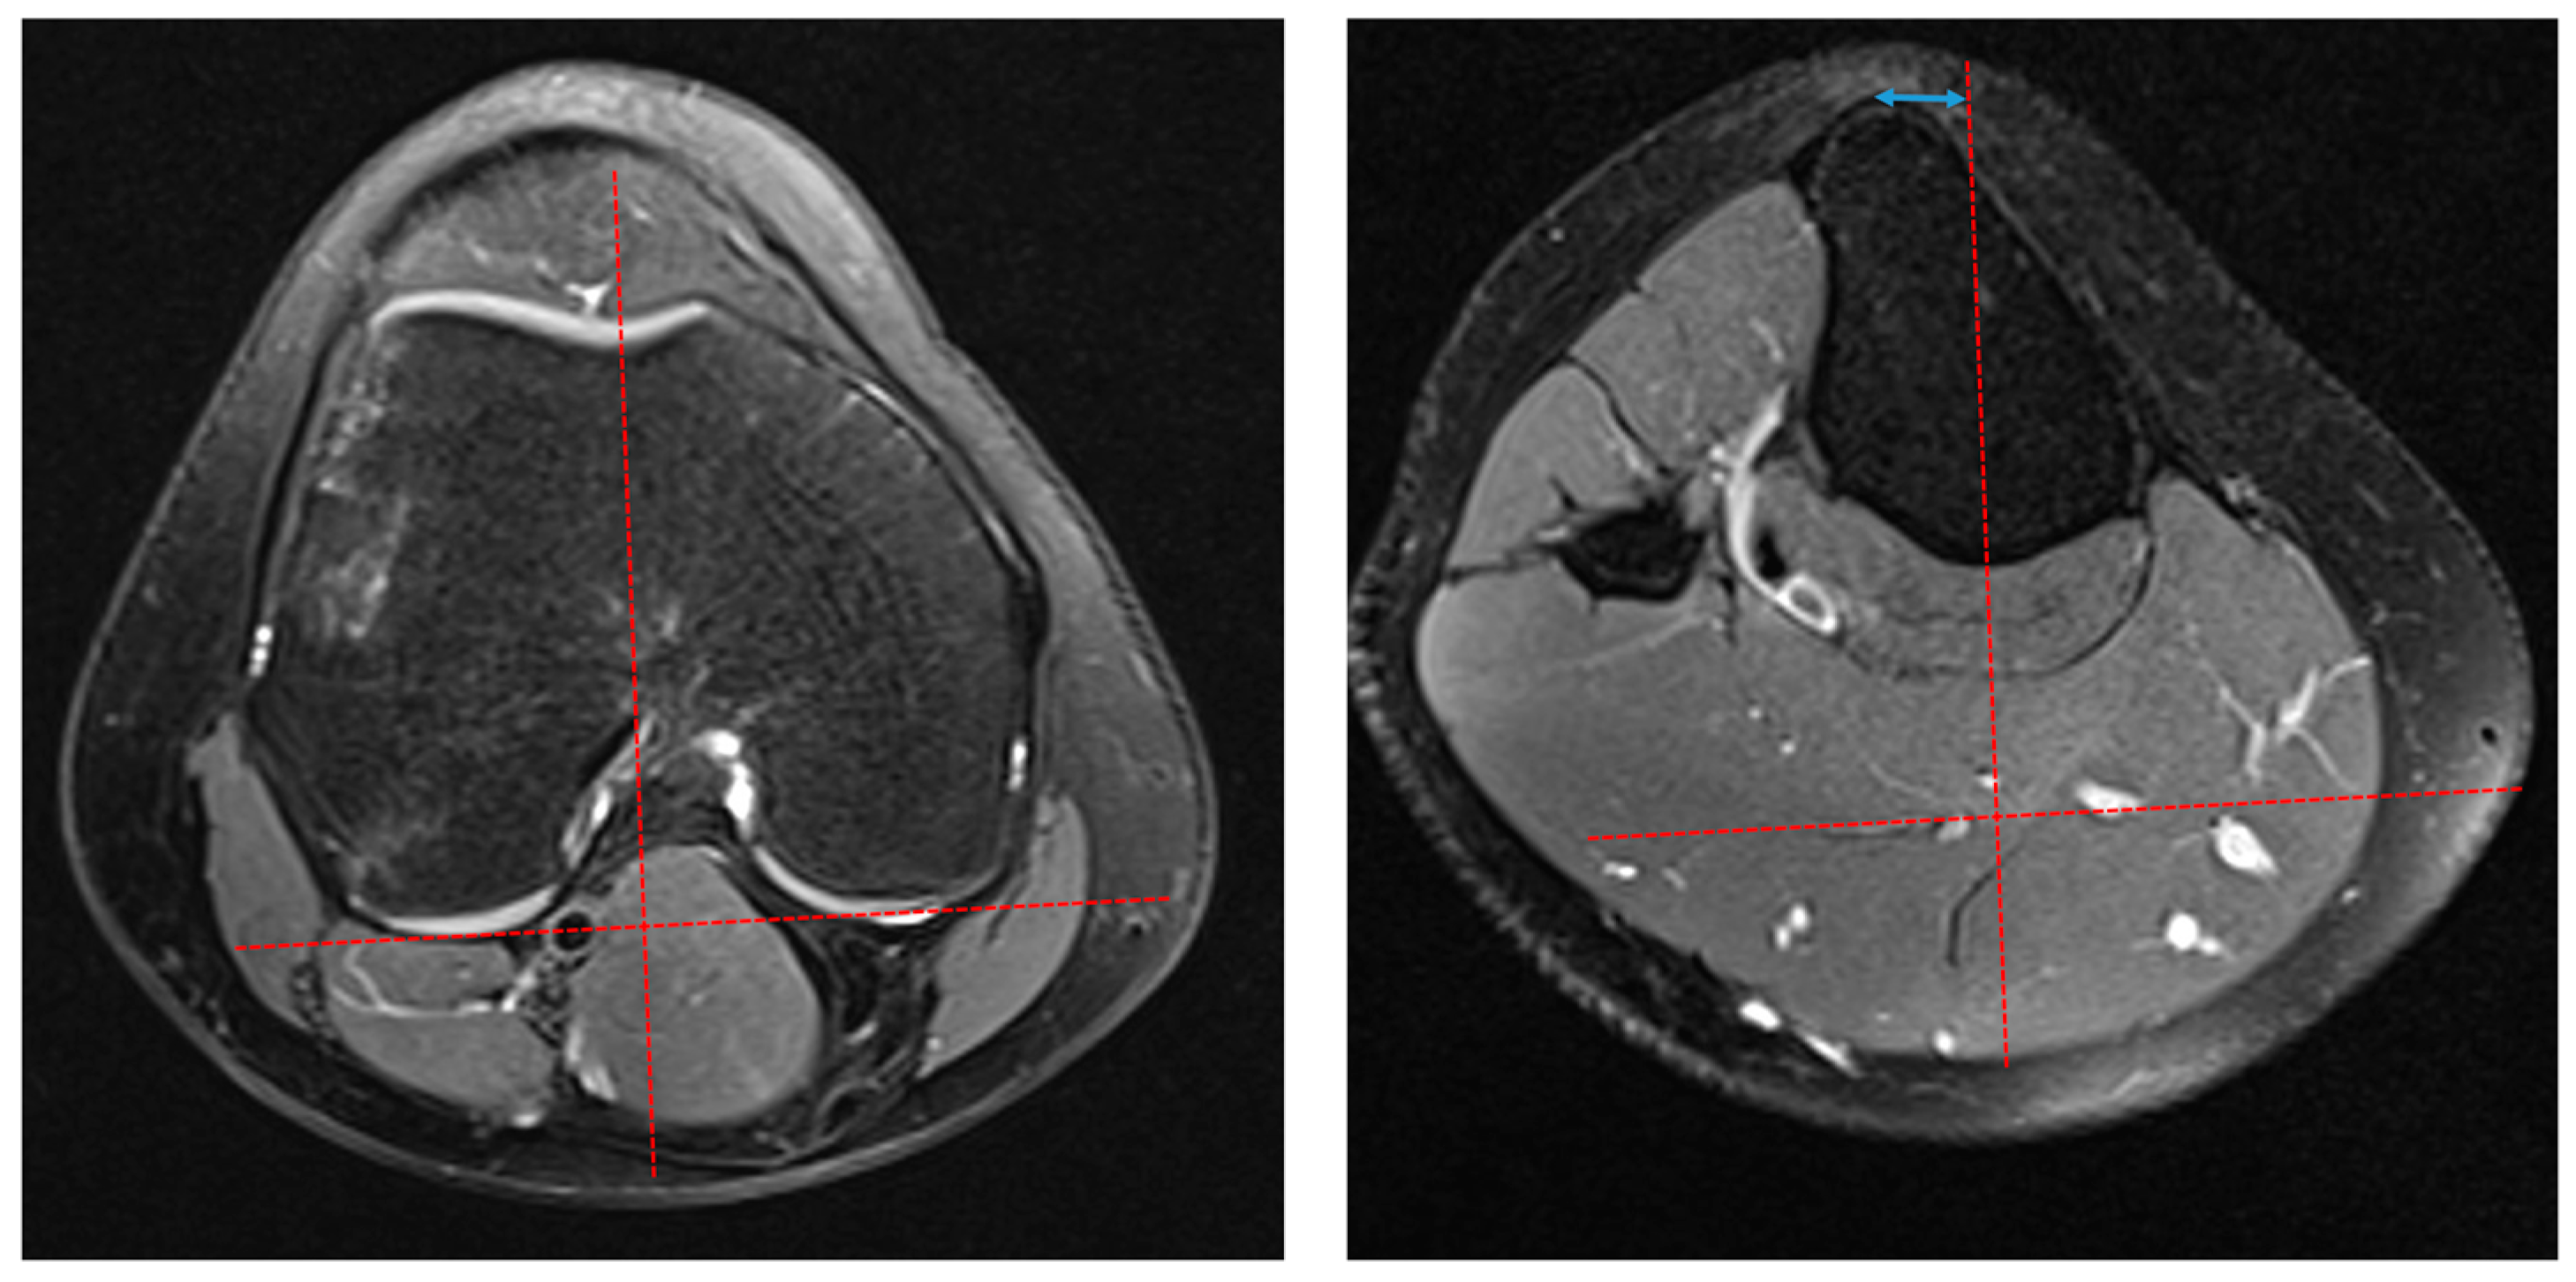

2.2. Radiological Measurement